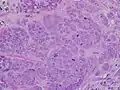

MRI showing breast cancer High-grade invasive ductal carcinoma, with minimal tubule formation, marked pleomorphism, and prominent mitoses, 40x field

High-grade invasive ductal carcinoma, with minimal tubule formation, marked pleomorphism, and prominent mitoses, 40x field Micrograph showing a lymph node invaded by ductal breast carcinoma, with an extension of the tumor beyond the lymph node

- Histopathology. Breast cancer is usually classified primarily by its histological appearance. Most breast cancers are derived from the epithelium lining the ducts or lobules, and these cancers are classified as ductal or lobular carcinoma. Carcinoma in situ is growth of low-grade cancerous or precancerous cells within a particular tissue compartment such as the mammary duct without invasion of the surrounding tissue. In contrast, invasive carcinoma does not confine itself to the initial tissue compartment.[135]

- Grade. Grading compares the appearance of the breast cancer cells to the appearance of normal breast tissue. Normal cells in an organ like the breast become differentiated, meaning that they take on specific shapes and forms that reflect their function as part of that organ. Cancerous cells lose that differentiation. In cancer, the cells that would normally line up in an orderly way to make up the milk ducts become disorganized. Cell division becomes uncontrolled. Cell nuclei become less uniform. Pathologists describe cells as well differentiated (low grade), moderately differentiated (intermediate grade), and poorly differentiated (high grade) as the cells progressively lose the features seen in normal breast cells. Poorly differentiated cancers (the ones whose tissue is least like normal breast tissue) have a worse prognosis.